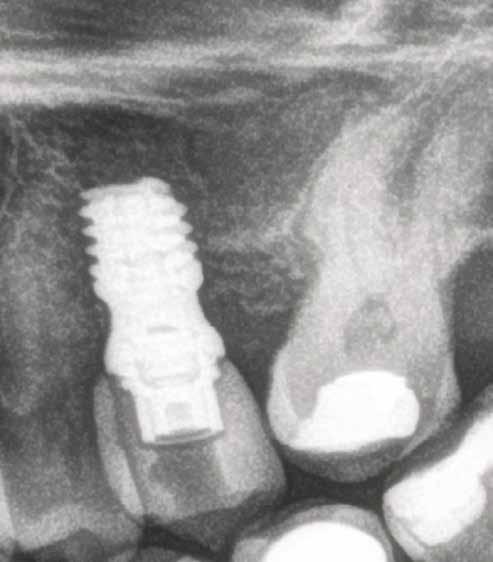

1. ábra: A műtét előtti szituáció, megfigyelhető az implantátumok közötti konkáv terület, ahova könnyen beragad az ételmaradék, és könnyen kialakul a periimplantitis.

Egy 47 éves páciens jelentkezett nálunk egy alsó, hátsó foghiánnyal, ahol jelentős csontfelszívódást tapasztaltunk a moláris fogak korábbi eltávolítása miatt (1. ábra). Két implantátum körül is volt ínyrecesszió, illetve a keratinizált íny mennyisége minimális volt (kevesebb, mint 1 mm). 4 hónappal az implantációt követően ínykorrekciót végeztünk.